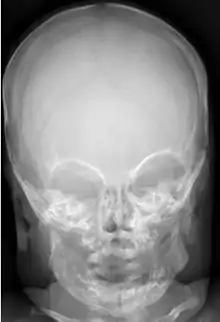

| An MRI of a patient with benign familial macrocephaly (male with head circumference > 60cm) | |